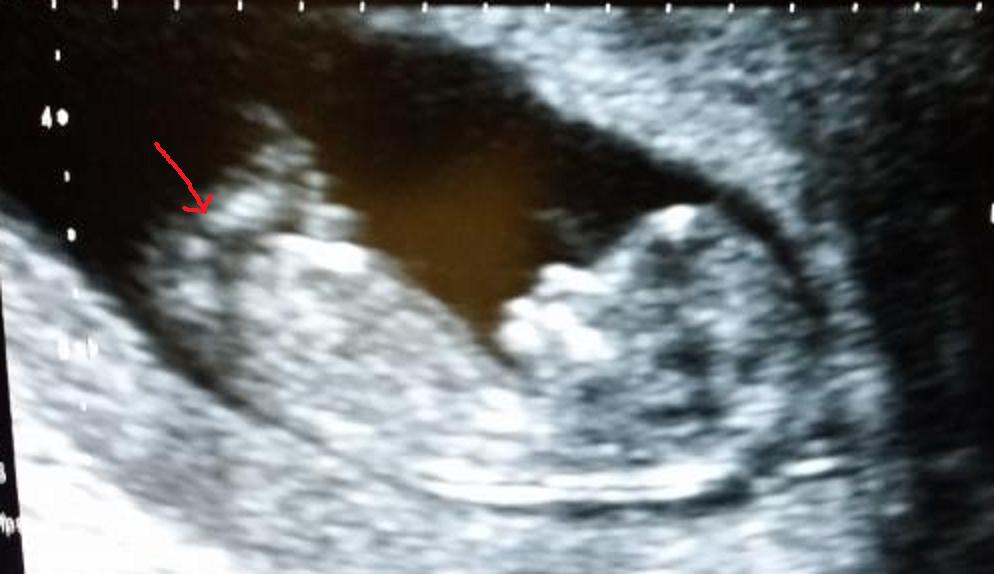

Hi i am guessing where i think the nub is but i could be very wrong. What do you think Boy or Girl? Attachment 21837

I'm thinking that the leg is actually blocking the nub. It's really busy down there and im having a hard time telling what is what. But I don't see anything I'd guess on.

I really don't see the nub in this shot, sorry!

no nub